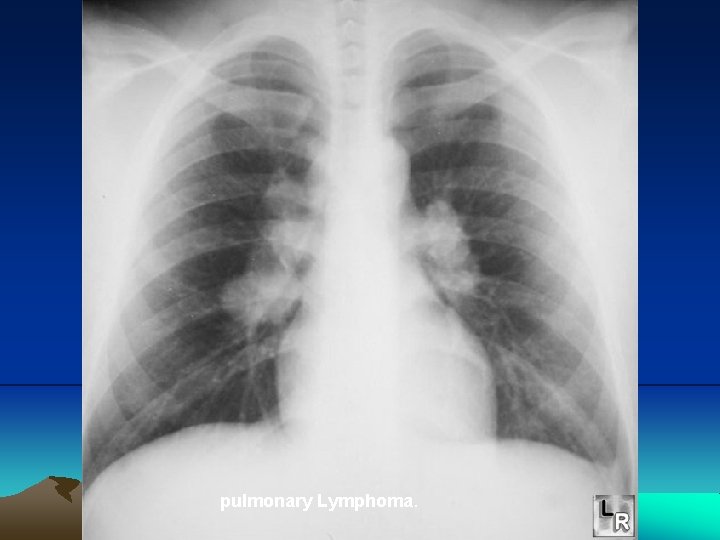

pulmonary Lymphoma.

pulmonary Lymphoma.